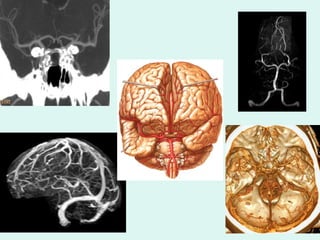

DIAGNÓSTICO POR IMAGEM ARTERIOGRAFIA ANGIO RM DOPPLER ANGIO TC

ANGIO RM Ótima resolução espacial,  Avaliação em 3 planos, Estudo do parênquima encefálico com uso concomitante de técnicas funcionais como difusão, perfusão, ativação cerebral, espectroscopia.  A angio-RM é realizada quando há tempo e indicação para melhor caracterização da lesão. Estudo dos sistemas arterial e/ou venoso intracranianos

ANGIO RM ARTERIAL

ANGIO RM VENOSA

TÉCNICAS FUNCIONAIS